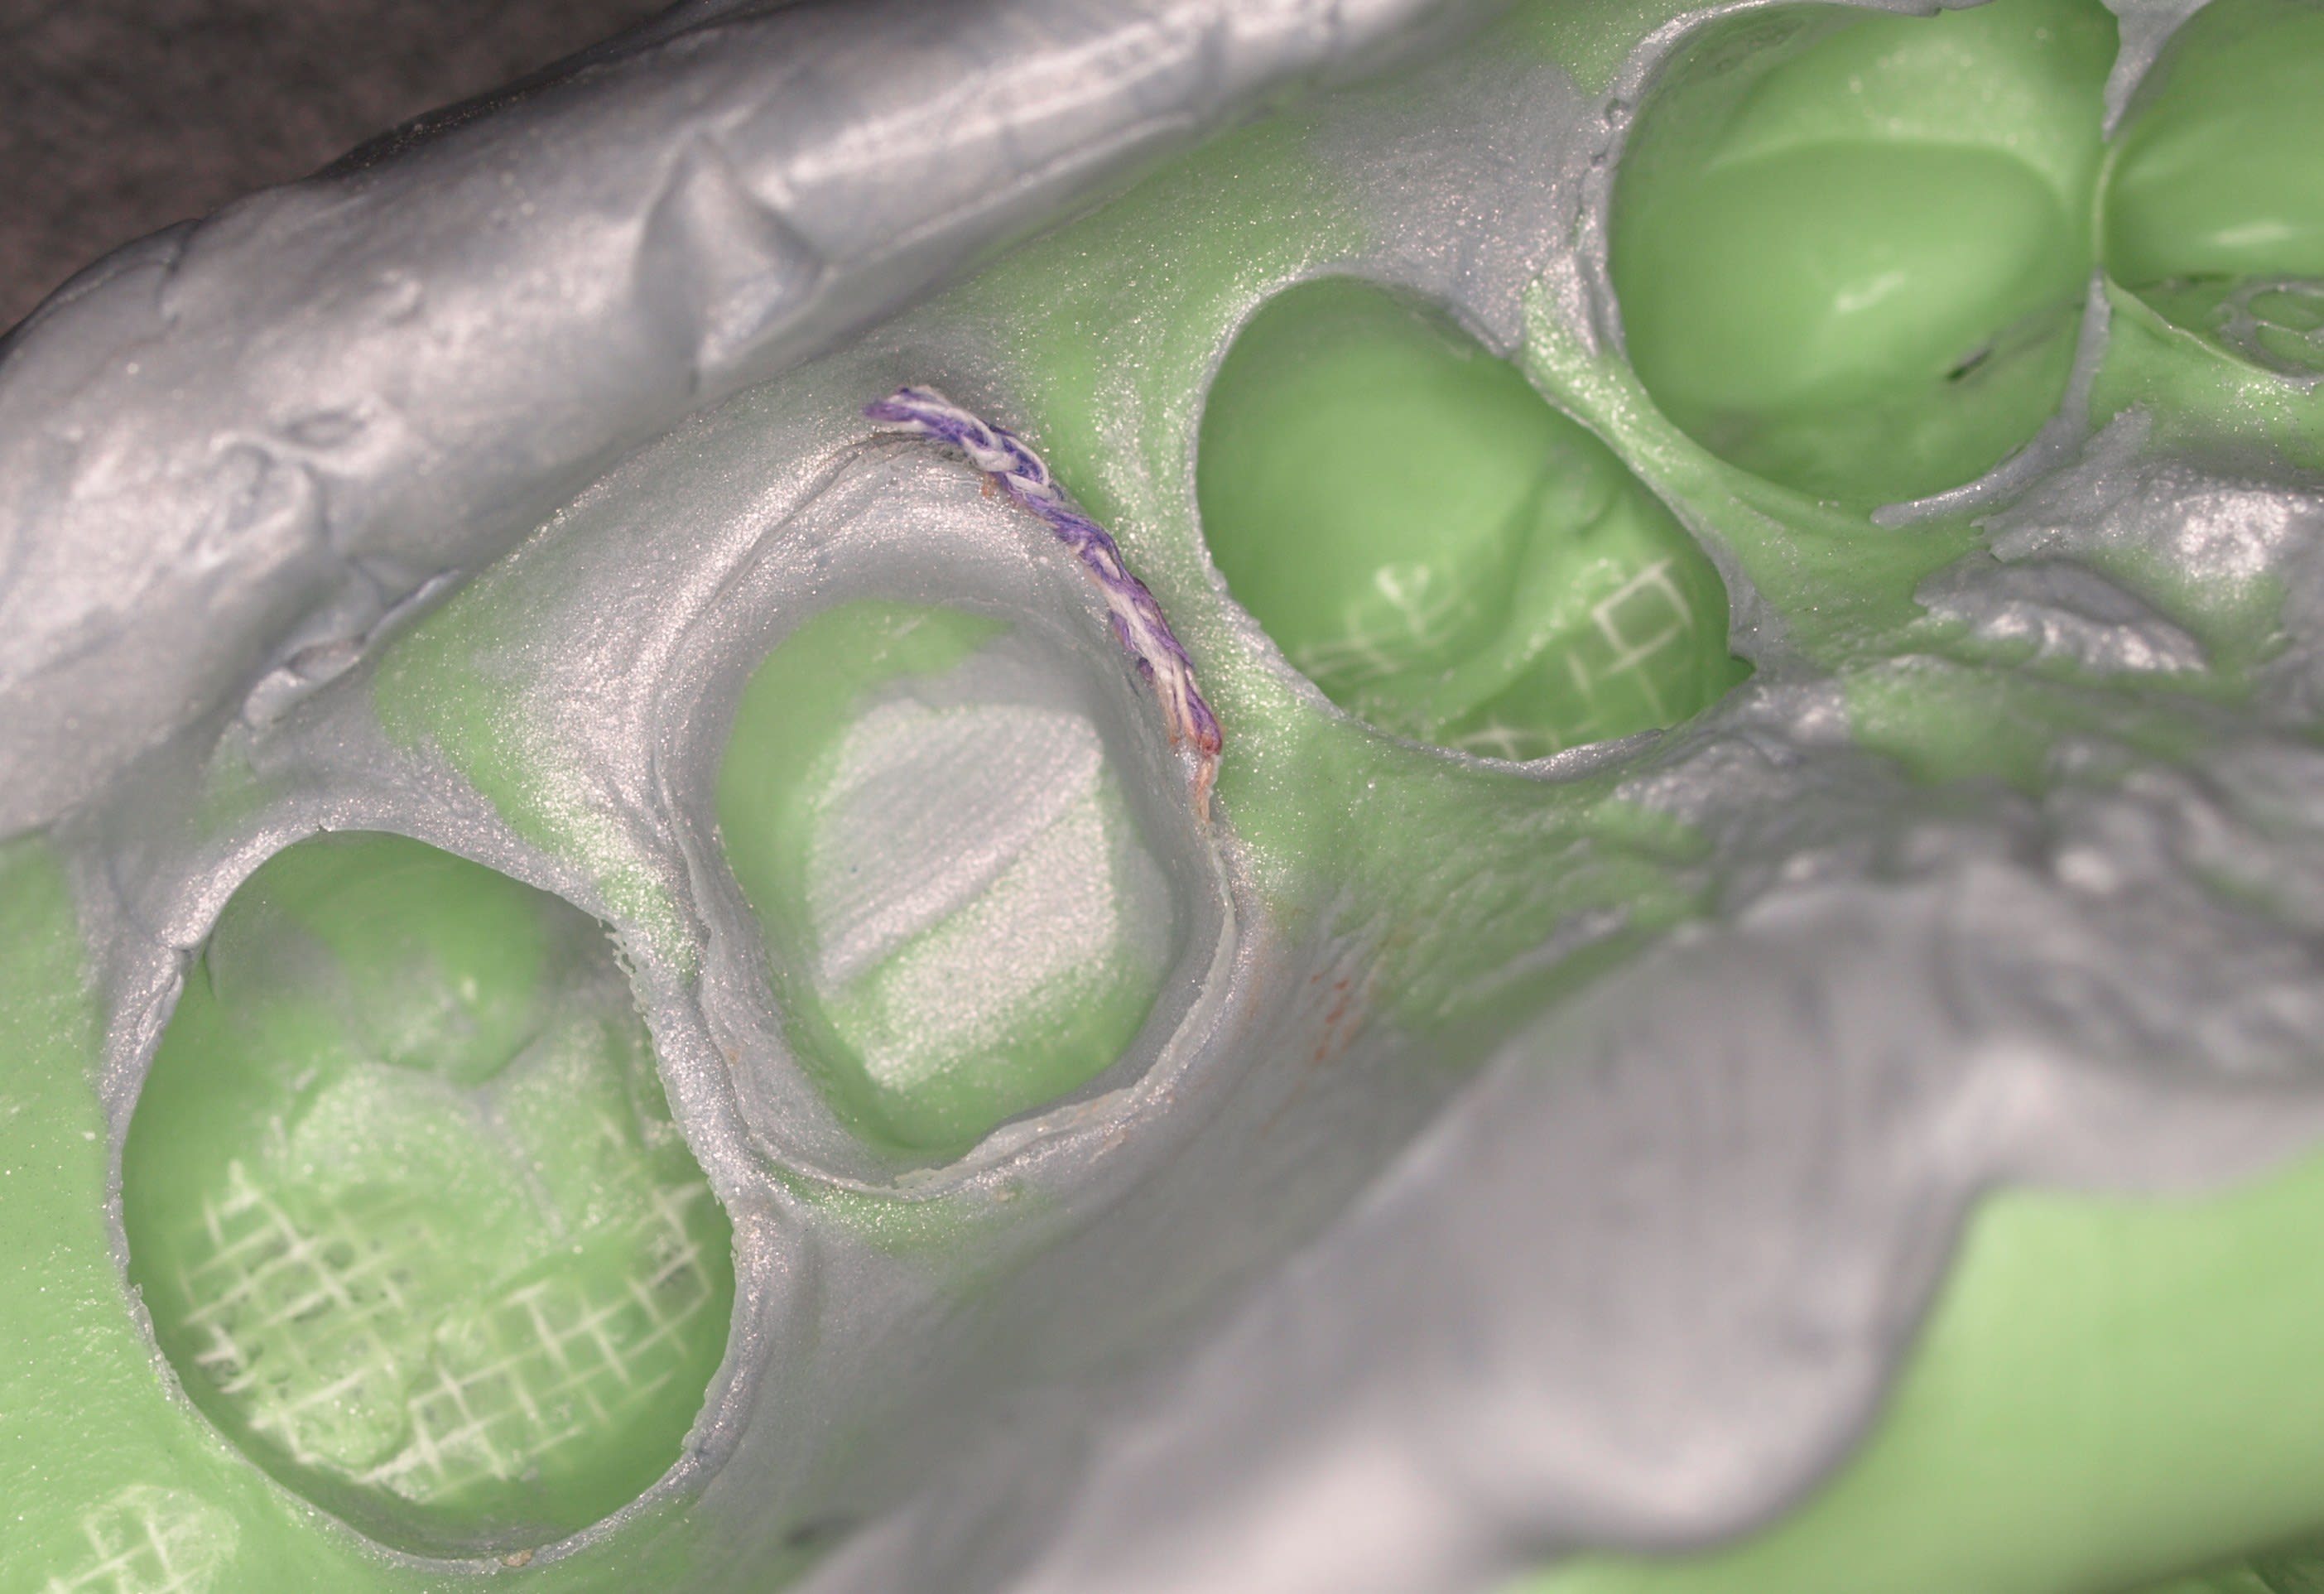

C est vrai ça ,c est un mordu compétition ?

3 couleurs :-)

Laisse moi deviner

On dirait un silicone d occlusion rigide ton machin violet .

Tu fais une wasch sur mordu ? Ou un double mélange associé au mordu rigide ?

Trop cher le PE ?, tu te juniorifies ?:-):-):-):-):-):-)

ça peut paraitre compliqué ; c'est vrai que ça prend du temps... Mais les rainures permettent au light et à l'extra light de s'écouler de manière optimale.

Cette technique me permet d'obtenir une empreinte (prise en deux temps) à la fois détaillée, fiable et reproductible. Mais surtout celle-ci me permet de savoir de suite si elle est déformée / compressive ou pas...

C'est un silicone A, avec du light et de l'extra-light... tout ce qu'il y a de plus classique en somme.

Mais, tu as l’œil enlaye... C'est un des silicone par addition les plus dur/rigide que j'ai pu testé. C'est pour moi le meilleur silicone qui existe, et en tout cas il convient parfaitement pour l'empreinte en deux temps.

Malheureusement, ils ne le vendent plus en France, alors je l'importe...

C'est pas une question de prix, l'empreinte-mordu a beaucoup d'avantage, mais tout dépend du cas ;-)